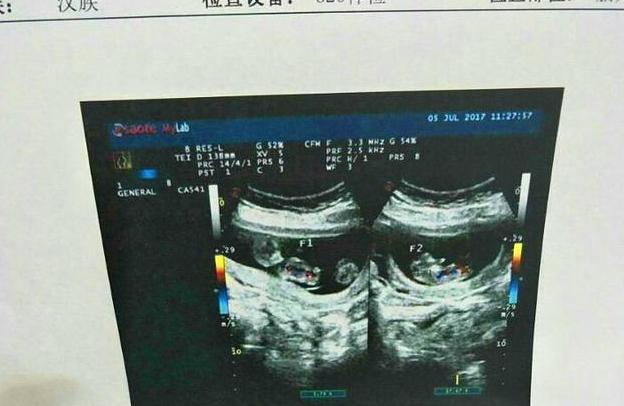

最后璐璐的总结是,如果前期肚子比较大,或者B超显示孕囊偏大一周或者两周,单胎变双胎的可能性要大一些,但也不是百分百,有些孕妈记错了末次月经,或者孕期营养太好,胎儿发育的偏大些也有可能呢,最后要按照B超为标准,如果出现“两胎儿雏形”,那就极有可能翻盘成功了。

对于这种情况,需要在确认双胞胎后多加检查,了解属于哪种类型的双胞胎,是单绒毛膜双胎还是双绒毛膜双胎,是同卵还是异卵,密切观察早期双胎的生长情况,如果出现一大一小,或者重量相差悬殊的情况,就需要及时处理,尽量避免变成单胎的情况。